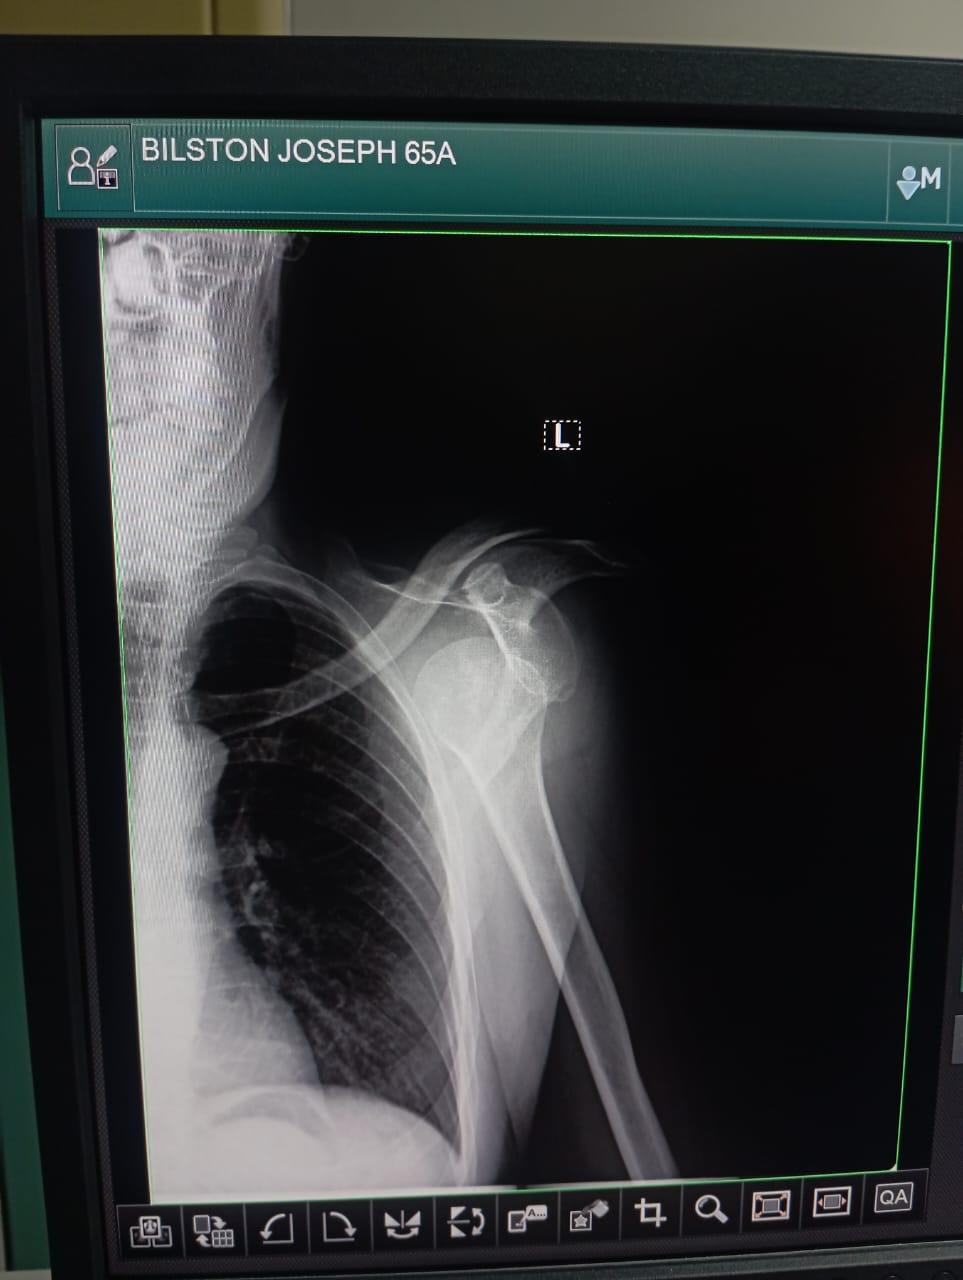

They found an english speaking travel guide who sat with me all night and when they put my arm back in my socket and he was able to translate that the doctors were sorry they did it without any pain medication. Because I had a drip in, they thought the nurse had already given it to me. The nurse thought that the doctors would do it. He also got hold of my daughters in Australia on a video call which was great. Although I was in a lot of pain it was nice to see them and show them I was okay (apparently thats not how it appeared to them). He took the photos of my before and after Xrays to show the doctors because that’s how it works over here. My arm felt much better back in it’s socket and not pressing against my ribs. And I am sure it was great entertainment for the dozens of people in the room with me.